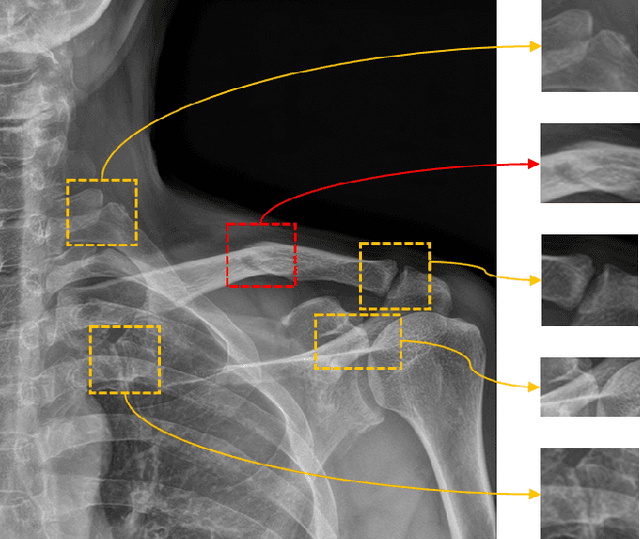

Abstract:Despite the success of deep learning in computer vision, algorithms to recognize subtle and small objects (or regions) is still challenging. For example, recognizing a baseball or a frisbee on a ground scene or a bone fracture in an X-ray image can easily result in overfitting, unless a huge amount of training data is available. To mitigate this problem, we need a way to force a model should identify subtle regions in limited training data. In this paper, we propose a simple but efficient supervised augmentation method called Cut\&Remain. It achieved better performance on various medical image domain (internally sourced- and public dataset) and a natural image domain (MS-COCO$_s$) than other supervised augmentation and the explicit guidance methods. In addition, using the class activation map, we identified that the Cut\&Remain methods drive a model to focus on relevant subtle and small regions efficiently. We also show that the performance monotonically increased along the Cut\&Remain ratio, indicating that a model can be improved even though only limited amount of Cut\&Remain is applied for, so that it allows low supervising (annotation) cost for improvement.